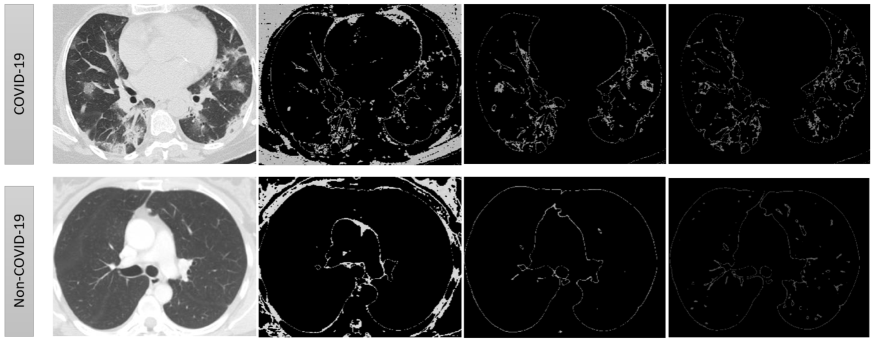

Thoracic radiology evaluations found high rates of ground-glass opacities and consolidations in COVID-19 patients. One can observe the ground-glass opacities (GGOs) together with consolidations in the CT-Scan of COVID-19 images. These regions are isolated with difference in shapes (left image in Fig. 8), which is captured by PDs associated to and . Moreover, these regions have unique shape in the intensity plot, see appearance of alps, saddle points in Fig. 8 (right image). These are recorded by PDs of Lower-star-filtration and .

3.1.2 PDs: Capturing the Visible

This filtered complex, defined in the previous section, is able to capture the key features of a CT-scan, like, peaks, variations in intensity, etc. Connected components and appearance of loops at different intensity levels are captured in the PD’s of , and respectively (see Fig. 10). The PDs of and for the images in Fig. 10 are given in Fig. 12. It is evident that the difference in their visual appearance is captured by these PDs.

A peak, which is topologically equivalent to tetrahedron, appear as points at (or near to) infinity-line in the PD of , that is, a persistent 2-dimensional void (see Fig. 11, 12).

Lower Star Filtration (LSF) captures key features about variation in intensities in an image. Local minimum and saddle points, in the intensity plot, are vital shape features (see Fig 11). These features are recorded using LSF. The birth time of a point in this PD is local minimum and death time is saddle point.

To record these changes, we construct a simplicial complex, say , in the following way. Each pixel is taken as a vertex, and there is an edge from one vertex to its neighbouring 8 (or less in case its an edge vertex) vertices. This allow us to construct the filtration where here is the pixel value of the vertex . Only the zero-dimensional PD is essential for our model development. The Fig.12 shows a major difference between the PDs associated to LSF of a COVID-19 and a non-COVID-19 CT-scan image.